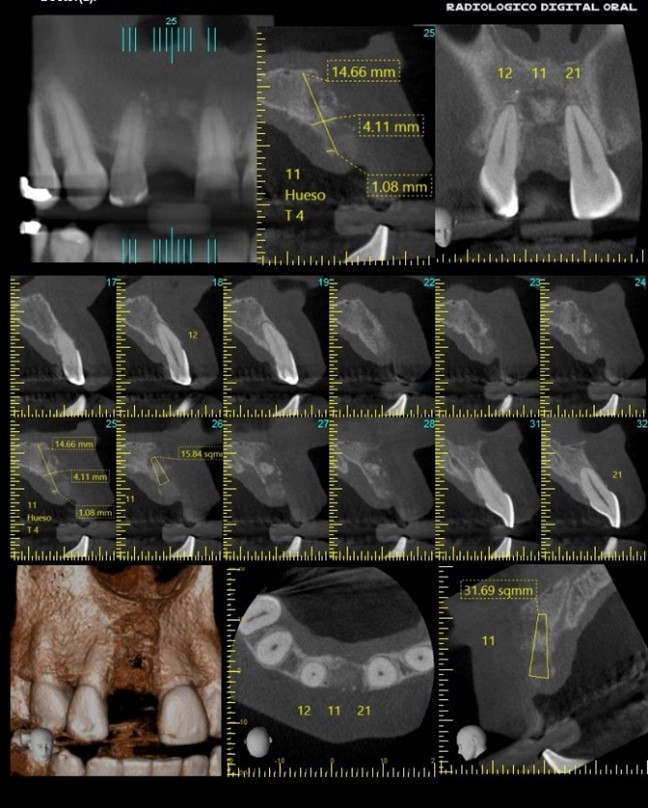

Paciente que presenta zona edéntula a nivel del 11 se le realiza tomografía, la cual podemos concluir que; zona sin diente con calidad de hueso tipo cuatro (Capa delgada de hueso cortical rodeando un núcleo de hueso trabecular de baja densidad). (Lekholm & Zarb). Reabsorción moderada a avanzada del reborde residual. Se realizan reconstrucciones tridimensionales y cortes multiplanares en 11, 12, 21, con mediciones en 11 (observar imagen anterior).